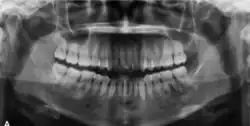

In its early stages, COF is often asymptomatic and may be incidentally detected on routine radiographic examinations. However, as it enlarges, it can cause swelling, facial asymmetry, pain, and sensory disturbances due to bone destruction. Radiographic findings vary based on the stage of the lesion, ranging from radiolucent to mixed or radiopaque appearances.[2]

Radiographically, COF appears as a well-defined unilocular lesion. In large mandibular cases, it may cause downward bowing of the inferior border.[13] Tooth displacement is common, while root resorption is less frequently observed.[13] If untreated, the lesion can grow substantially. Surgically, COF is usually well-demarcated from the surrounding bone and often easily enucleated. Some lesions may also exhibit a distinct capsule.[11]

In its early stages, central ossifying fibroma (COF) appears as a small, well-defined radiolucent lesion due to its fibrous tissue content. Differential diagnoses at this stage include periapical pathology, central giant cell granuloma, and ameloblastoma.[22][23] As the lesion matures, it exhibits a mixed radiolucent-radiopaque appearance due to progressive calcification.[22] At this stage, it should be differentiated from other mixed jaw lesions such as fibrous dysplasia, calcifying epithelial odontogenic tumour, adenomatoid odontogenic tumour, and condensing osteitis.[22] In its mature form, COF may appear predominantly radiopaque, resembling lesions like odontomas, osteoblastomas, or osteosarcomas radiographically.

COF typically presents with well-defined, smooth, and often corticated borders. As a central lesion, it originates within the medullary bone and expands concentrically in all directions.[24] With growth, it may cause tooth displacement, root resorption, inferior displacement of the mandibular canal, and loss or alteration of the lamina dura of adjacent teeth.[25]

In conclusion, COF most commonly occurs in the mandible and expands from a central epicenter. Radiographically, it presents as a well-defined mixed-density lesion,[26] and Cone Beam CT (CBCT) plays a crucial role in its accurate diagnosis and assessment.

Central Ossifying Fibroma (COF) typically presents as a painless swelling in the posterior mandible, though maxillary involvement can also occur.[31] Larger lesions may lead to facial asymmetry and displacement of adjacent teeth.[32] Radiographically, COF appears as a well-circumscribed, mixed radiolucent–radiopaque lesion with a characteristic sclerotic border, and the degree of radiopacity reflects the stage of mineralization.[33] Cone-beam computed tomography (CBCT) offers detailed evaluation of cortical expansion, root displacement, and internal architecture.[34]